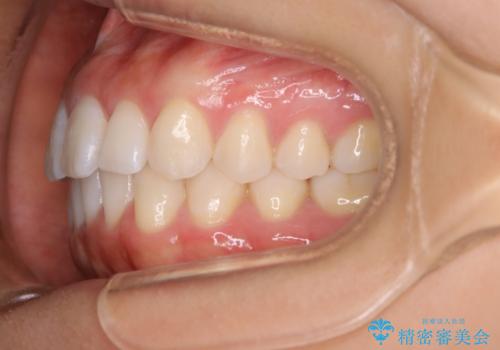

インビザライン矯正 前歯のすきっ歯を治したい

- 上顎の前歯のすきっ歯を治したいとのことで来院されました。

前歯の隙間を閉じる矯正治療の場合、インビザライン適用症例のためインビザラインによる治療をご提案しました。

後戻り防止のため、上唇小帯切除も併用しています。

上唇と歯ぐきを結ぶひも(上唇小帯)が長いと、前歯に隙間が空いてしまうことがあります。今回は隙間を確実に閉じる目的、また矯正後に再び隙間が空かないように、上唇小帯の切除も行っています。